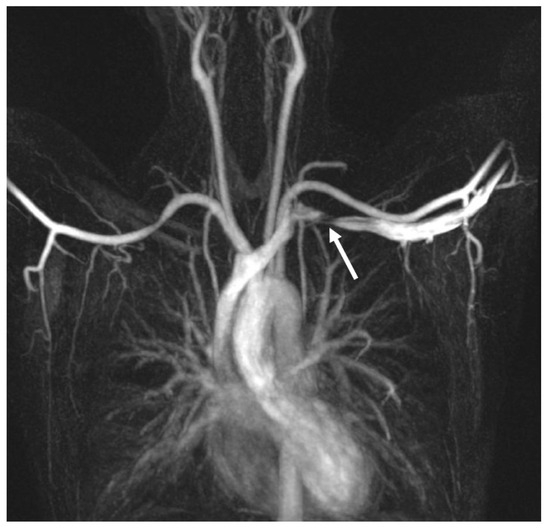

4.4. Magnetic Resonance Imaging